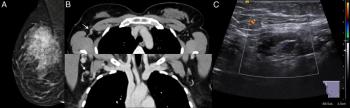

The combination of magnetic resonance imaging (MRI) and computed tomography (CT) had a 63.83 percent sensitivity rate for tumor-infiltrated axillary lymph nodes in patients with breast cancer in comparison to a 36.11 percent sensitivity rate for the combination of mammography and sonography.